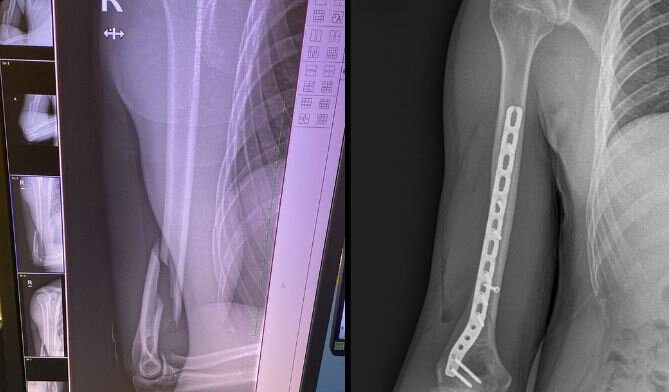

Mantuu сломал руку: «Теперь во мне титановая пластина и винты»

Mantuu сломал руку.

«Я сломал руку. Теперь во мне титановая пластина и винты», – подписал снимки руки до и после операции Матеуш «Mantuu» Вильчевски.

Поляк пообещал, что поделится подробностями перелома позже.